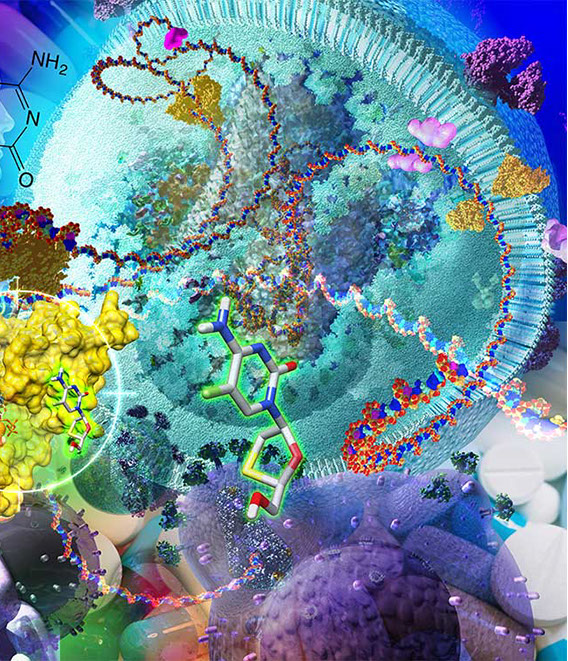

INSIDE /OUT, 2006

Visualization of the workings of the cell. Interior graphics for UCSD Biomedical Library.

INSIDE /OUT

The Workings of the Cell Installation at the UCSD Biomedical Library.

INSIDE /OUT

The Workings of the Cell Installation at the UCSD Biomedical Library

Emory Mural 4th Floor

Mural installed on the 4th floor of new Emory University Health Sciences Research Building. The focus on cutting edge research into small molecule inhibitor of viral RNA synthesisfor the treatment Hepatitis C and HIV viruses.

BIO commissioned me to create this mural for their main office lobby in Washington, D.C. It is called “Life Machine: A look inside: an artist’s visualization of the interior of a human cell.

Emory Science Research Building, 4th floor

Detail from the mural highlighting the HIV research of the 4th floor